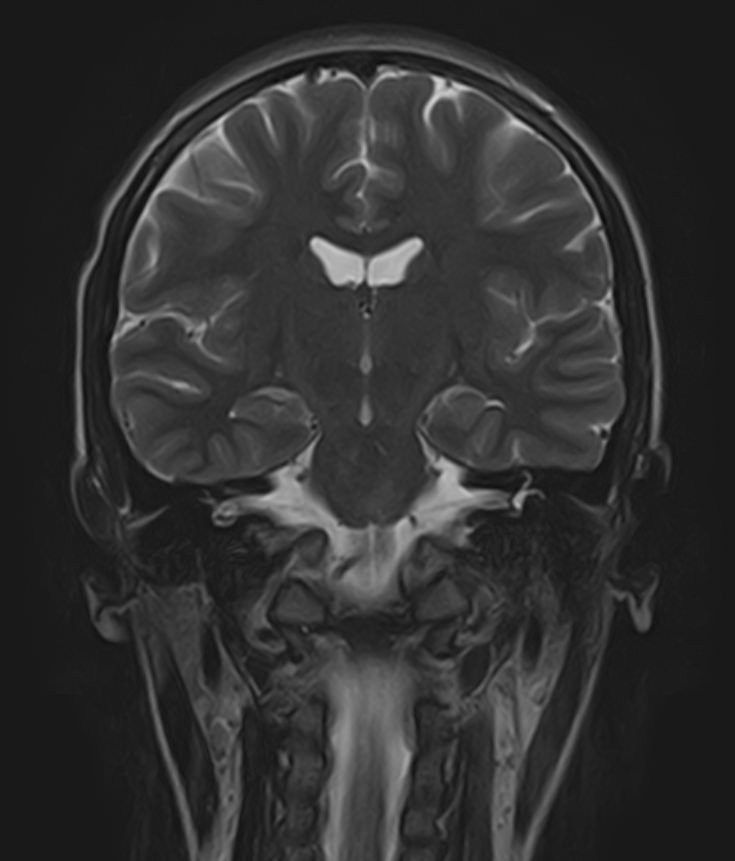

В клинике «Доступная медицина» можно пройти комплексное обследование, включающее в себя два протокола сканирования близко расположенных друг от друга анатомических областей – шейного отдела позвоночника и головного мозга. Метод комплексного обследования оценивает состояние всех структур головного мозга и самого верхнего сегмента позвоночного столба, который включает в себя 7 шейных позвонков, спинной мозг с отходящими от него нервными корешками и окружающими мягкими тканями.

Сканирование проводится на современном высокопольном магнитно-резонансном томографе закрытого типа TOSHIBA VANTAGE TITAN 1,5 Тесла. Магнитно-резонансный томограф производит послойное сканирование исследуемой зоны в разных плоскостях, затем при помощи компьютерных программ преобразует полученные данные в трехмерные изображения с высокой степенью детализации.

В рамках проведения данного комплексного исследования можно выявить:

• очаги ишемического и геморрагического инсульта, область поражения, признаки отека головного мозга, стадию развития заболевания;

• доброкачественные и злокачественные новообразования, их точную локализацию, стадию развития процесса, проводить динамическое наблюдение за опухолевым процессом на фоне лечения;

• признаки демиелинизирующих заболеваний (рассеянный склероз), выявить очаги поражения миелиновой оболочки нервных волокон, определить стадию заболевания;

• характерные признаки дегенеративных заболеваний головного мозга (болезнь Альцгеймера, старческая деменция, болезнь Паркинсона), определить изменения коры головного мозга и подкорковых структур;

• поражение структур головного мозга на фоне травм, гематомы головного мозга;

• изменения, характерные для психических расстройств различного генеза (эндогенных и экзогенных), после вирусных инфекций, черепно-мозговых травм, отравлений токсическими веществами, на фоне наследственных заболеваний;

• остеохондроз, спондилоартроз, спондилез, межпозвонковые грыжи, унковертебральный артроз, сколиоз, усиленный или выпрямленный лордоз как нарушение статической функции позвоночника, травмы, аномалии позвоночника.